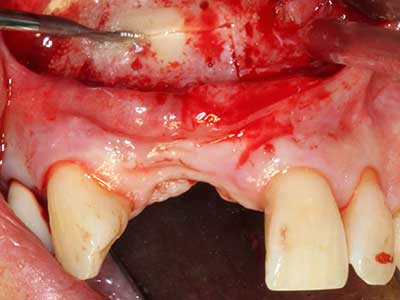

Пиезохирургията има допълнителни предимства при събиране на костни блокове. В допълнение към високата прецизност при остеотомията, описана по-горе, употребата на фините режещи накрайници значително намаляват загубата на материал. Голяма загуба на материал по време на събиране може да се очаква с дебелите накрайници, особено при употреба на борери Линдеман (Lakshmiganthan, Gokulanathan et al. 2012). Базалното разделяне, което е необходимо, особено за присадка на блок при ретромолар, е улеснено от специално създадени правоъгълни триони. В резултат на това, пиезохирургията е разглеждана като прецизна, улеснена и безопасна процедура за събиране на костни блокове в ретромоларното пространство (Happe 2007) (Фиг. 1-12).

Индикация: Костно разделяне/ шиниране?

Костната тъкан е не само минерализирана структура, тя съдържа и съществено количество колагенови влакна. Това означава, че тя има не само добра компресивна сила, но и известна степен на гъвкавост, която може да се възприеме като предимство при извършване на костна аугментация. В класическата процедура по разширяване чрез костно разделяне, атрофиралият алвеоларен гребен е разделен надлъжно и внимателно разширен след достигане на подходящата остеотомна дълбочина (Фиг. 13-16), в идеалния случай без допълнително отстраняване на периостеума (Brugnami, Caiazzo et al. 2014, Stricker, Fleiner et al. 2014). Системите с винт и пластини с увеличаване на разстоянието при разширяване са доказали ефективността си при разделяне на двете костни ламели, оставайки под прага на фрактурите. В общи линии, оставащата ширина на костта от поне 3–4 mm е задължителна (Chiapasco, Zaniboni et al. 2006), за да се гарантира добра гъвкавост и достатъчно костно покритие за бъдещото поставяне на импланти. Ако е необходимо, вертикалната остеотомия на едната или двете страни може да подобри гъвкавостта. Комбинацията с допълнителни техники за аугментация, особено в букалната страна, е описана като алтернатива на класическата техника.

Процедурата по разделяне е атравматична и няма голяма загуба на пространство, използвайки пиезотриони, и няма значителна разлика между импланти в разделени челюсти и импланти в алвеоларния гребен без костен дефицит (Chiapasco, Zaniboni et al. 2006, Danza, Guidi et al. 2009). Въпреки това, важно е да има достатъчно и продължително охлаждане, особено при ограничено и дълбоко разделяне, за да се избегне термичен стрес в апикално-остеотомните зони.